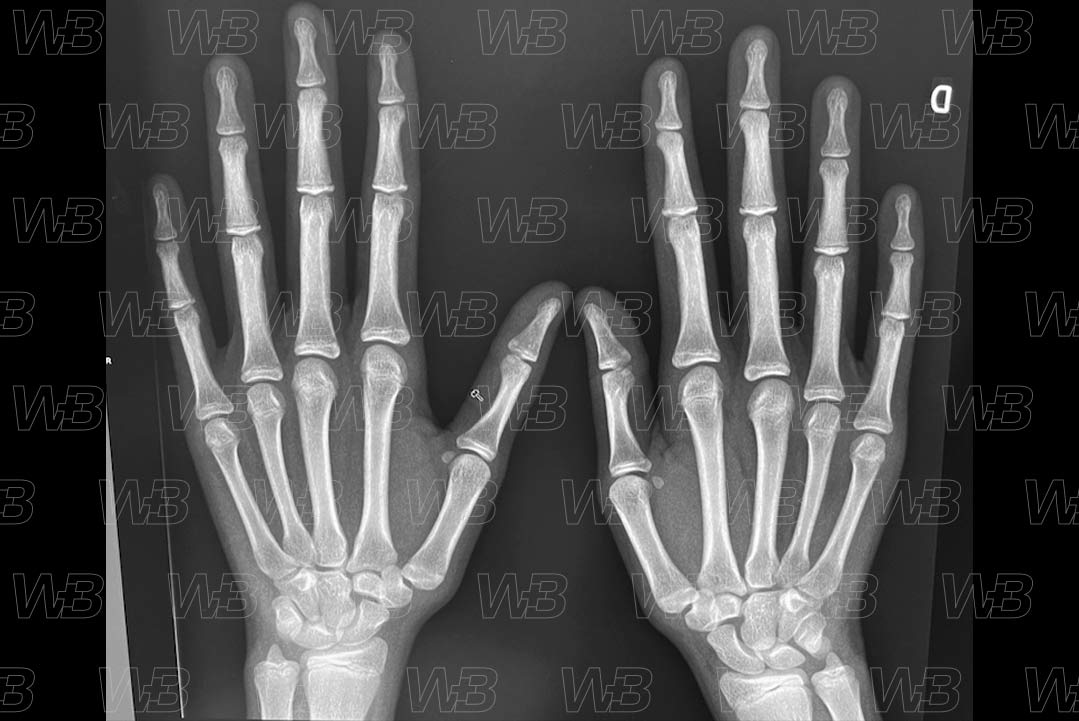

Atlas idade óssea - Feminino - 14 anos

RADIOGRAFIA MÃOS E PUNHOS [cms-watermark]

Feminino

14 anos:

• Fusão da epífise do primeiro metacarpo.